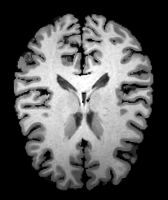

Image Manual Seg DA-1 Mono-21 DA-21 Mono-65 Refer to caption Refer to caption Refer to caption Refer to caption Refer to caption Refer to caption

Figure 2:  Examples of knee MRI registration (top) and brain MRI segmentation (bottom) results. Top: The first two columns are the moving image/segmentation and the target image/segmentation followed by the warped moving images (with deformation grids)/segmentations by different models. Bottom left to right: original image, manual segmentation, and predictions of various models. Mono-i𝑖i and DA-i𝑖i represent the mono- and DA models with i𝑖i manual segmentations respectively.

Image Manual Seg DA-1 Mono-5 DA-5 Mono-200 Refer to caption Refer to caption Refer to caption Refer to caption Refer to caption Refer to caption

Figure 4: Examples of brain MRI registration (top) and knee MRI segmentation (bottom) results. Top: The first two columns are the moving image/segmentation and the target image/segmentation followed by the warped moving images/segmentations by different models. Bottom left to right: original image, manual segmentation, and predictions of various models. Mono-i𝑖i and DA-i𝑖i represent the mono- and DA models trained with i𝑖i manual segmentations respectively.